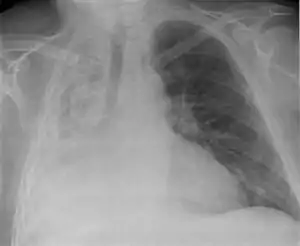

Atelectasis of a person's right lung

Atelectasis is the collapse or closure of a lung resulting in reduced or absent gas exchange. It is usually unilateral, affecting part or all of one lung.[2] It is a condition where the alveoli are deflated down to little or no volume, as distinct from pulmonary consolidation, in which they are filled with liquid. It is often called a collapsed lung, although that term may also refer to pneumothorax.[1]

Clinically significant atelectasis is generally visible on chest X-ray; findings can include lung opacification and/or loss of lung volume. Post-surgical atelectasis will be bibasal in pattern. Chest CT or bronchoscopy may be necessary if the cause of atelectasis is not clinically apparent. Direct signs of atelectasis include displacement of interlobar fissures and mobile structures within the thorax, overinflation of the unaffected ipsilateral lobe or contralateral lung, and opacification of the collapsed lobe. In addition to clinically significant findings on chest X-rays, patients may present with indirect signs and symptoms such as elevation of the diaphragm, shifting of the trachea, heart and mediastinum; displacement of the hilus and shifting granulomas.[10]